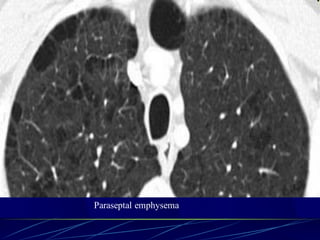

Paraseptal (distal acinar)

emphysema

Affects the peripheral parts of

the secondary pulmonary lobule

Produces subpleural lucencies.

Paraseptal emphysema